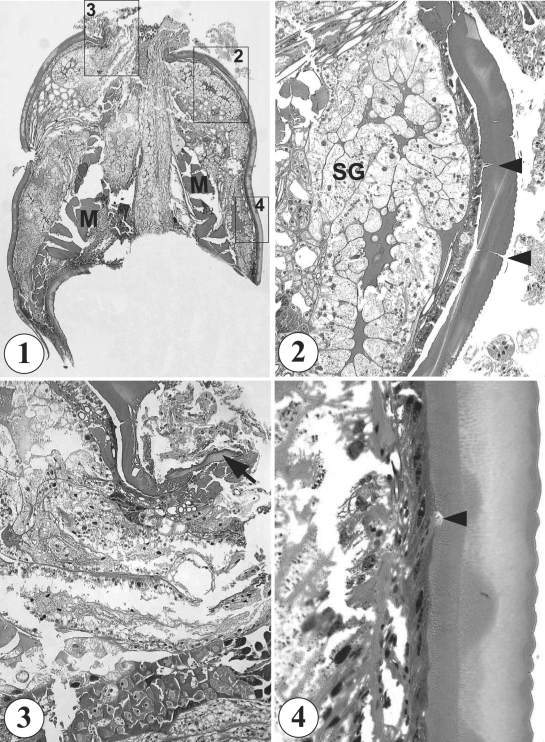

In light microscopic observations of the sections, the mass appeared to be a part of a round to elliptical-shaped organism (0.8 × 0.6 cm), and looked like a pentastomid, or an arthropod, without containing any structure of host origin (Fig. 1). It was finally identified as a species of hard tick, presumably belonging to family Ixodidae. It had a non-segmented body, well developed skeletal musculature of 160 µm in thickness in the middle part of the body (Fig. 1), well developed salivary glands in anterior half of the body (Fig. 2), and a capitulum (Fig. 3). Its external surface was covered with a thick cuticle of about 80 µm in thickness, which consisted of 5 layers, including an outermost thin layer with saw-like annulations, 3 inner layers of different thickness and structures, and the innermost layer with pore canals (Fig. 4). No legs were found sectioned.

Similar misinterpretation of tick infestations as masses of other origins is at times encountered (Pyeon and Kim, 1987). In such a case, the tick is sectioned and histological slides are made, in which case the diagnosis becomes more difficult. Nevertheless, sectional morphologies of ticks are scarcely available among the world literature. Pyeon and Kim (1987) described morphological characteristics of the cuticle layer of a hard tick based on 50 serial sections. The cuticle was composed with 5 layers, including the outermost layer characterized by saw-like annulations and the innermost basal layer having many glandular structures with basophilic granules and connected with outside through pore canals (Pyeon and Kim, 1987). In our case, the morphology of the cuticle is almost identical with the previous report of a hard tick (Pyeon and Kim, 1987). The presence of well developed musculatures and salivary glands supports the diagnosis. Moreover, in our specimens, small pieces of the capitulum were found sectioned near the anterior end of the body, and thus the capitulum is suggested to be protruded out of the anterior end of the body. By contrast, in soft ticks, the capitulum is extended from some distance beneath the anterior end of the body (Belding, 1965).